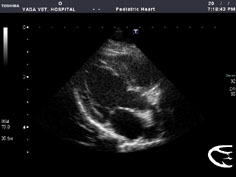

心エコー検査

心エコー検査とは、超音波エコー画像診断装置で心臓の様子を動画像で映し出して診断する検査です。心臓の形状の異常を診る「形態的診断」と心臓の働きや血液の流れの異常を診るを診る「機能的診断」があります。心臓の異常を診断したり、心臓病の程度や進行具合をチェックするのに非常に有効な検査です。

左上段:健常犬・左心室長軸画像

右上段:健常猫・左心室長軸画像

左中段:フィラリア寄生犬・右短軸肺動脈画像

右中段:末期フィラリア症による肺高血圧症犬

・肺動脈流速計測

左下段:PDA(動脈管開存症)犬・肺動脈内血流検査

(ドプラーカラーフローマッピング+流速計測)

右下段:VSD(心室中隔欠損症)犬・短絡血流検査

(ドプラーカラーフローマッピング)